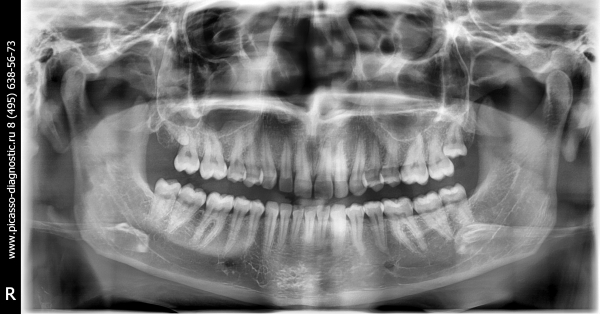

Я сделала ОПТГ. Сейчас нет возможности сходить к доктору.

Видно ли какие-то отклонения от нормы на фото?

По снимку всё нормально.